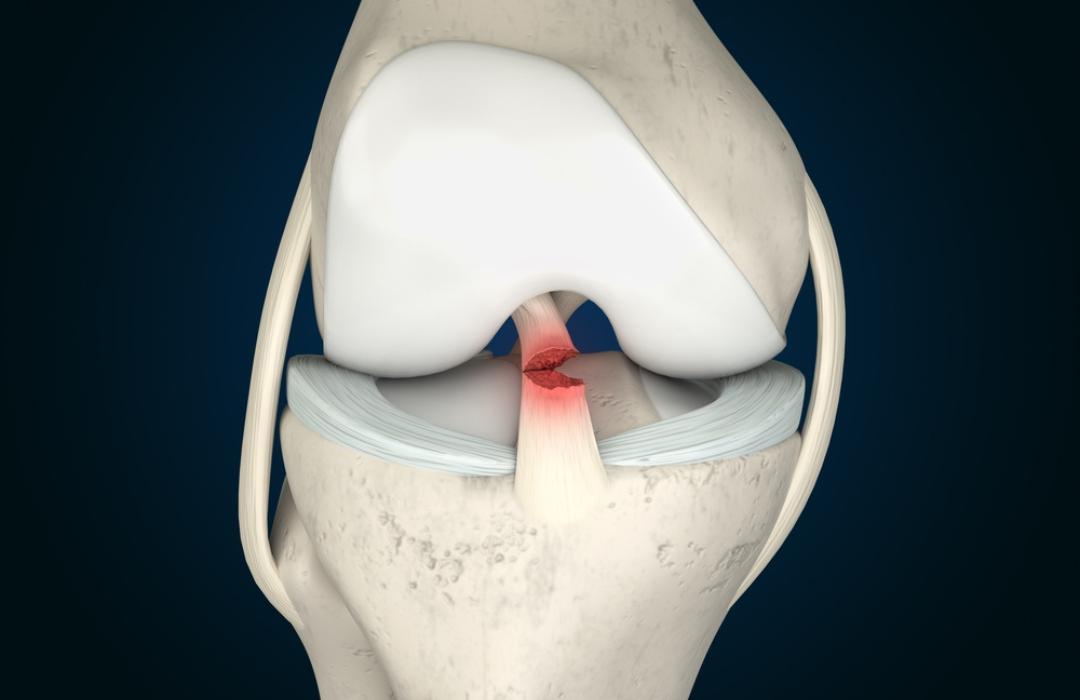

As lesões dos ligamentos cruzados — anterior (LCA) e posterior (LCP) — comprometem a estabilidade do joelho e podem causar falseios, dor, dificuldade para correr e insegurança ao caminhar ou realizar movimentos bruscos.

O tratamento cirúrgico consiste na reconstrução do ligamento rompido utilizando enxertos, que substituem a estrutura original.

a reconstrução do LCA ou LCP devolve firmeza ao movimento, reduzindo episódios de falseio e aumentando a segurança nas atividades diárias.

ao estabilizar o joelho, o procedimento reduz o risco de lesões secundárias, como rupturas de menisco e desgaste da cartilagem.